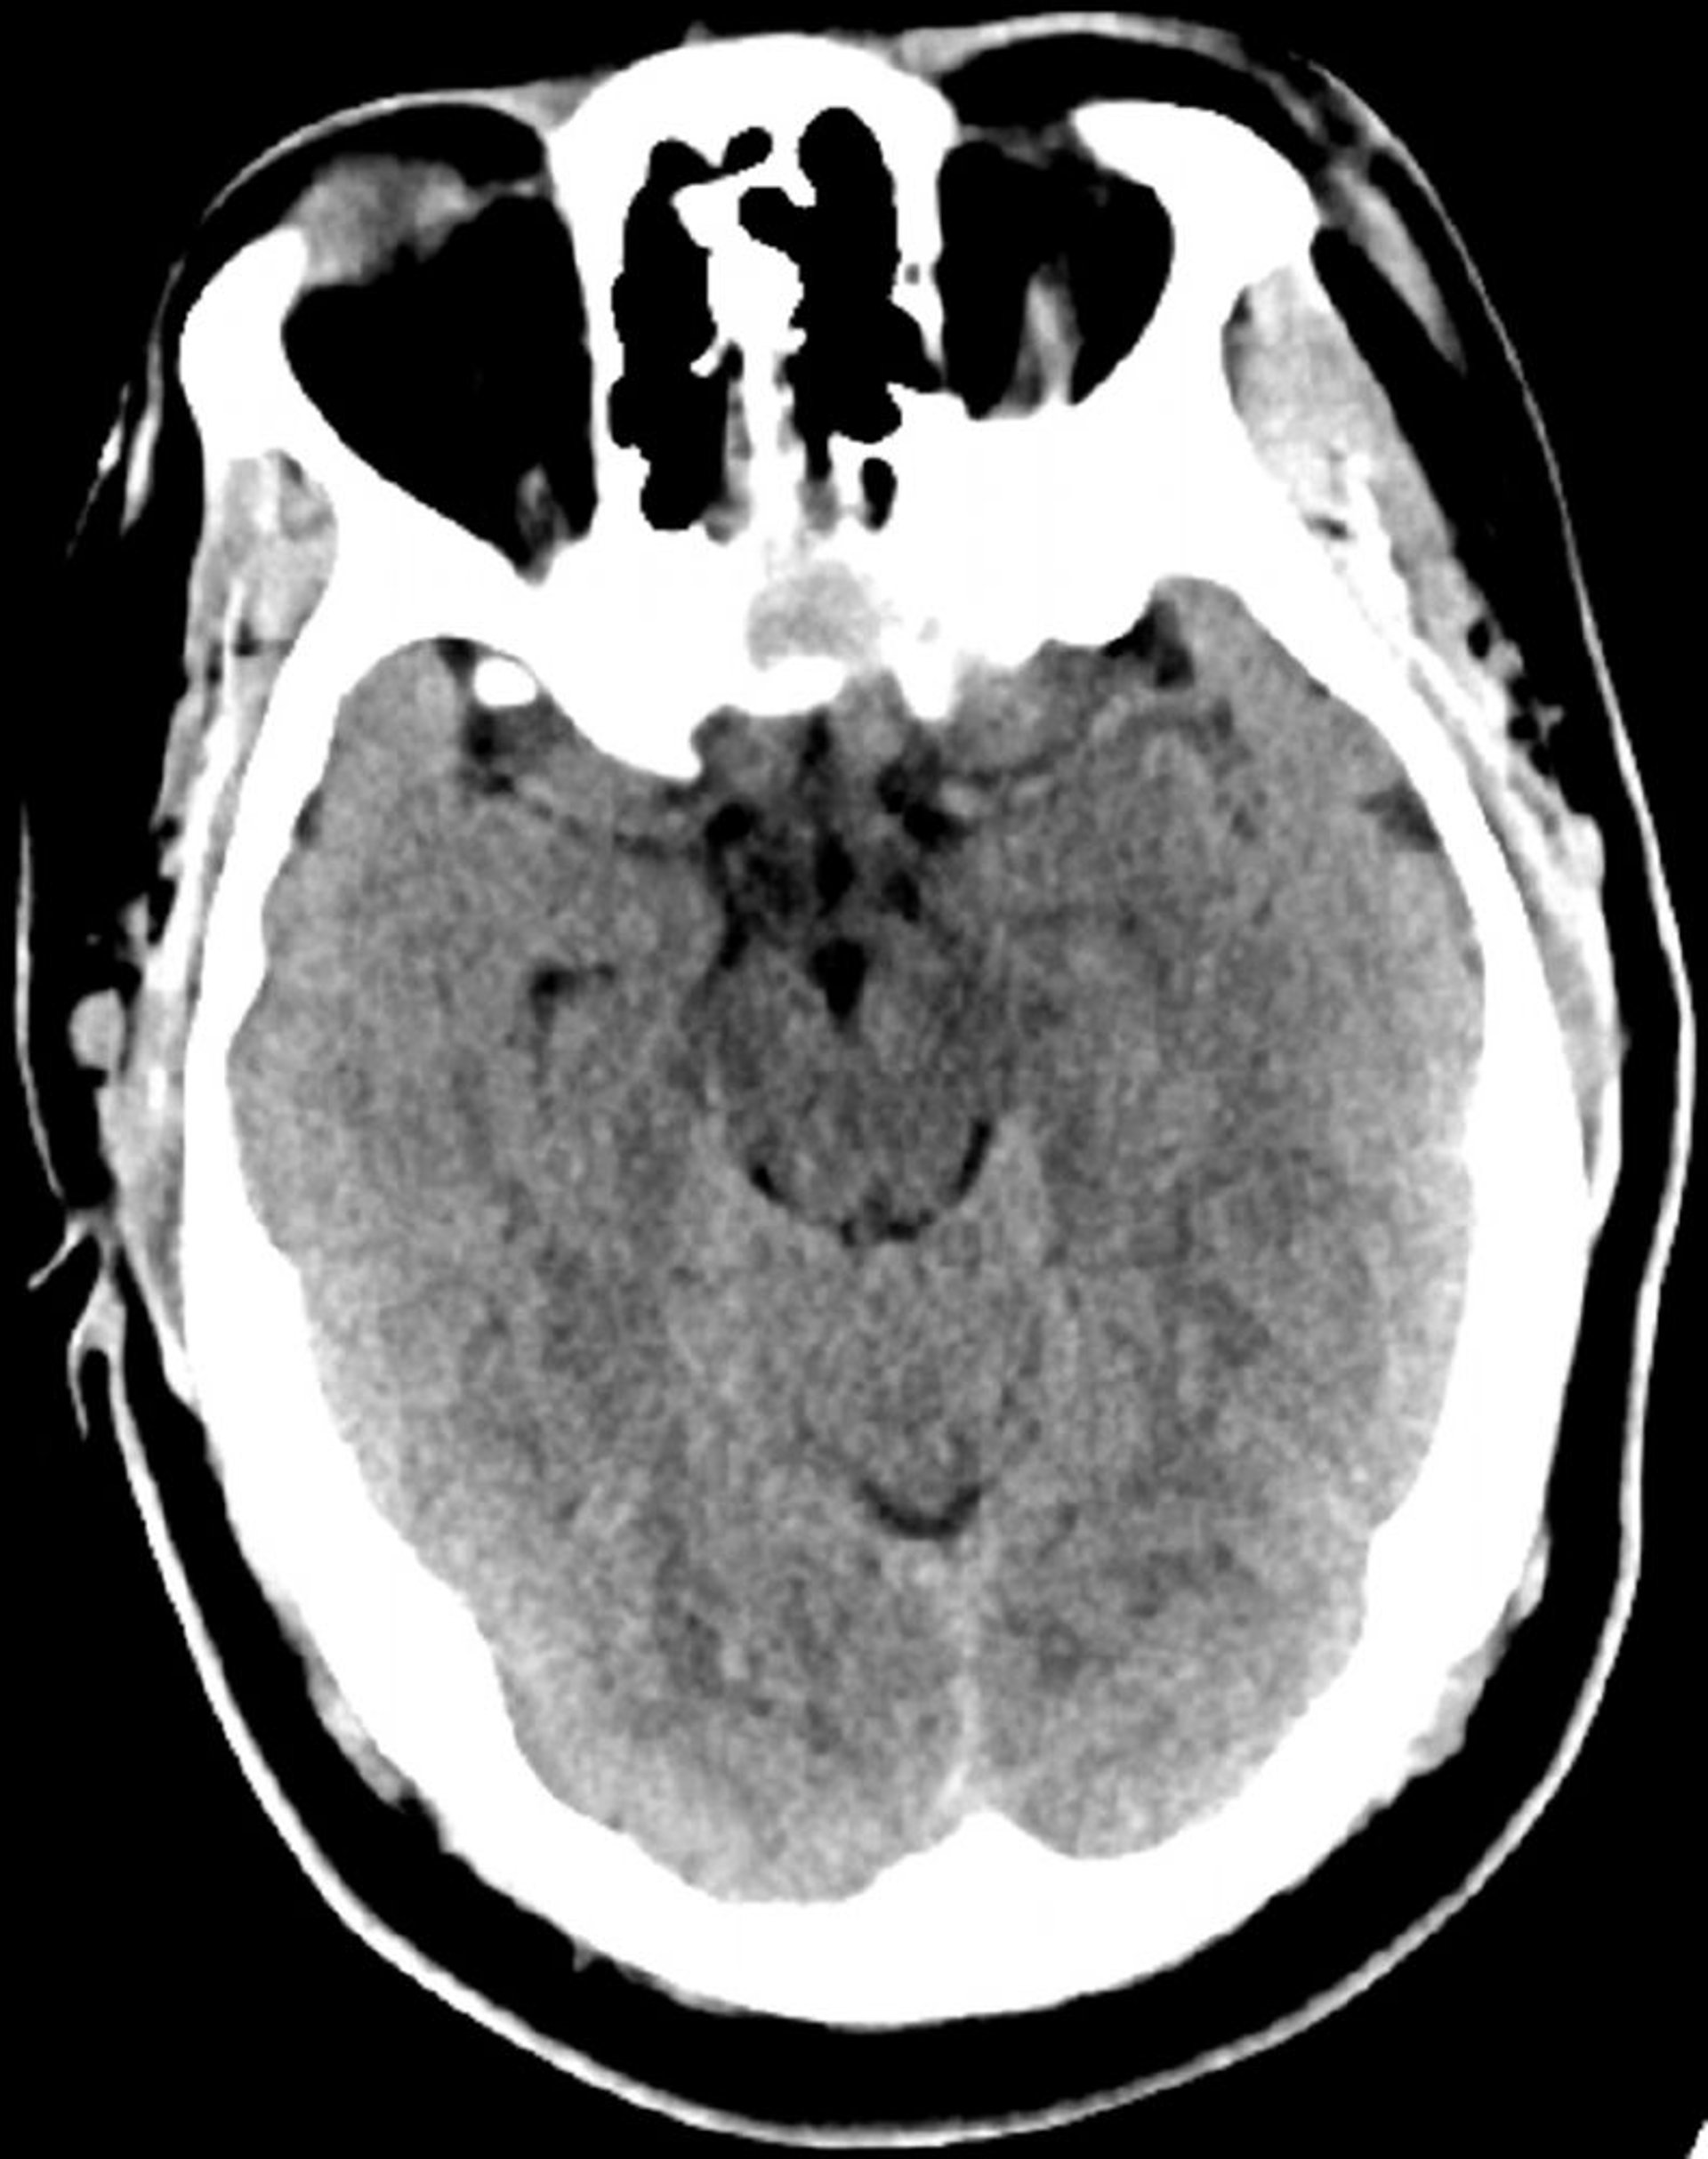

Normal Head CT Scan (Adult, Age 30) – Slide 6

This image is a normal CT scan of the head of a young adult aged 30. There is no intra- or extra-axial fluid or hemorrhage. Grey-white differentiation is preserved. Ventricular size and sulcal pattern are normal.